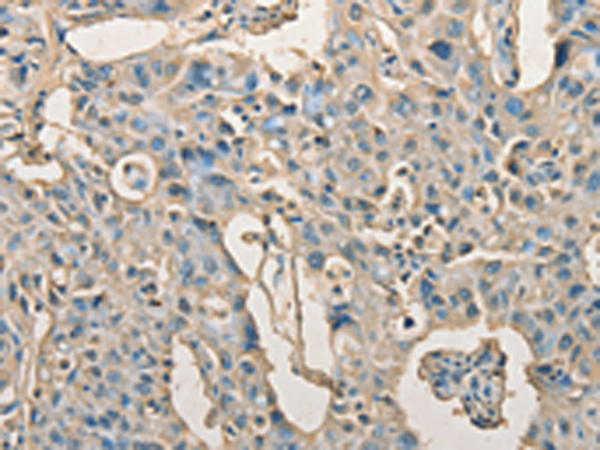

分类: 科研抗体货号: P07794别名: GA; AGU; ASRG应用: WB,IHC反应种属: Human, Mouse, Rat